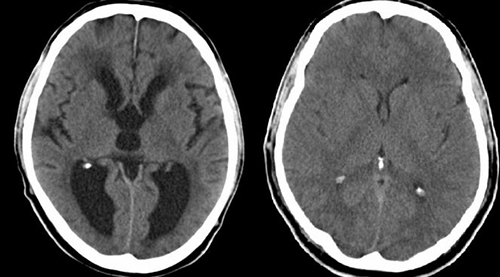

Нарушение оттока жидкости из мозговой ткани связано с дефектом эпендимы. При гидроцефалии, встречающейся у одного из 2000 новорожденных, мозговая жидкость задерживается в камерах головного мозга. Это приводит к увеличению размеров головы и повреждению мозговых тканей. В 2013 г. ученые из Немецкого центра изучения рака в Хайдельберге открыли ген под названием Mpdz, вызывавший у мышей гидроцефалию. Затем исследователям из Саудовской Аравии удалось найти человеческий аналог этого гена. Теперь в Германии выяснили механизм, который вызывает развитие болезни.

Ученые из Хайдельберга, наблюдая за лабораторными животными, обнаружили, что с геном Mpdz связано нарушение проницаемости эпендимы - мембраны, отделяющей мозговую ткань от ликвора. Дефект вызывает нарушение оттока жидкости из мозговой ткани и развитие гидроцефалии. Подробно об исследовании сообщает журнал EMBO Molecular Medicine.